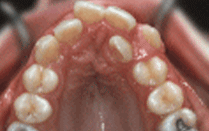

康贝佳口腔推出隐形矫正技术,患者可以在医生的指导下,通过3D椅旁系统看到自己牙齿畸形的状况,并且通过屏幕可以看到牙套将要如何安装,如何施力矫正。打破传统治疗“铁嘴钢牙”,为您量身定做一系列透明矫治器,只需每2周更换一副,就可以让原来的“老虎牙”、“龅牙”;等令您难堪的牙齿在不被人发觉的情况下得到有效的矫正和改变。而该技术矫正的时间更短,就可以轻松舒适的让难看的牙齿统统“立正、站齐”。>>>牙齿矫正要多久>>>